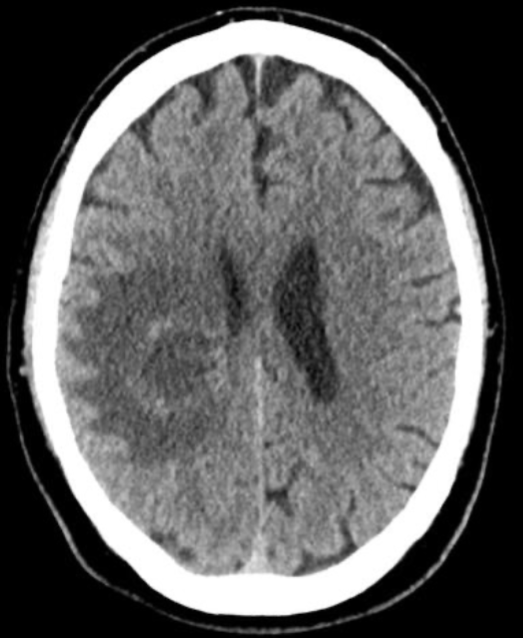

Name the pathology

Intracerebral haemorrhage (bleed)